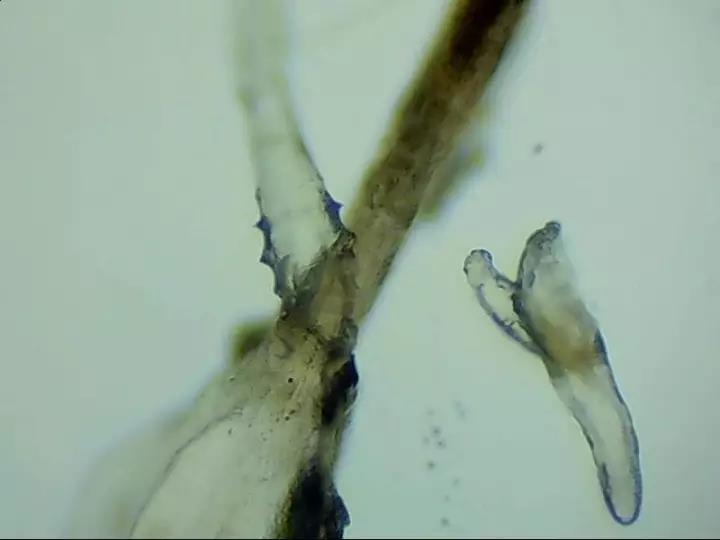

近年来针对干眼症的研究让更多人认识干眼症,也清楚控制泪液分泌和排出的一系列器官和干眼症息息相关,但看到电子显微镜下的照片后,人们还是会发出这样的疑问:我得干眼症和螨虫有关系吗?2017/11/28 9:25:18